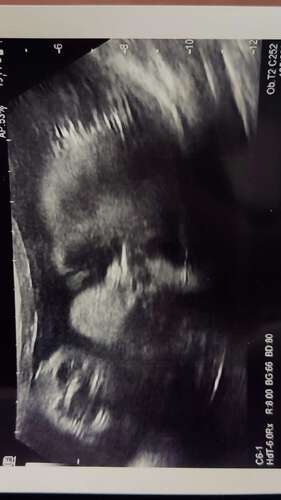

Net toevallig gezien bij mij meisje echt leuk 馃グ

Bij onze dochter ook duidelijk te zien op dr echo..bij haar geboorte meteen een bos haar馃槃. Inmiddels is ze bijna 3 maanden en heeft ze hele schattige blonde krulletjes

Ons meisje had dat ook! Meteen een enorme bos donkere krullen en nu na 3,5 maand nog steeds dezelfde volle bos 馃グ

Jaaa wij zagen ook veel haartjes op de echo 馃グ hij had al lange haartjes bij de bevalling en ondertussen een lekkere krullenbol 鉂わ笍

Ja!! En ook uiteindelijk de meeste haartjes op de plek waar we het op de echo zagen

Hier ook haartjes gezien op de echo en baby werd geboren met een echte Elvis kuif.